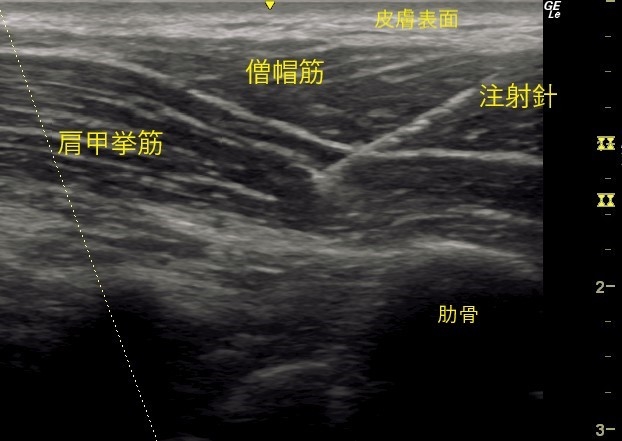

首肩では筋層がいくつか重なっています。

一般的な肩こりでは、中間層、もしくはより深層の筋肉に負担がかかっているという問題が存在します。

そこで中間層、深層まで針を入れて薬液注入する必要があるのですが、エコー等を見ないとどこに入っているか分かりません。

また、ブラインドで注射すると大血管や、肺、神経などに刺してしまう危険が増大します。

首肩こりにおいて、筋肉のどこに負担がかかっているのかエコーで見つけることができます。

つまり首肩こりを診断できます。

当院では、首肩こりの患者さんにどの辺りがこっているかを伺い、その該当する筋肉をエコーで調べ負担のかかっている箇所の筋腹に確実にボトックス注射をすることになります。